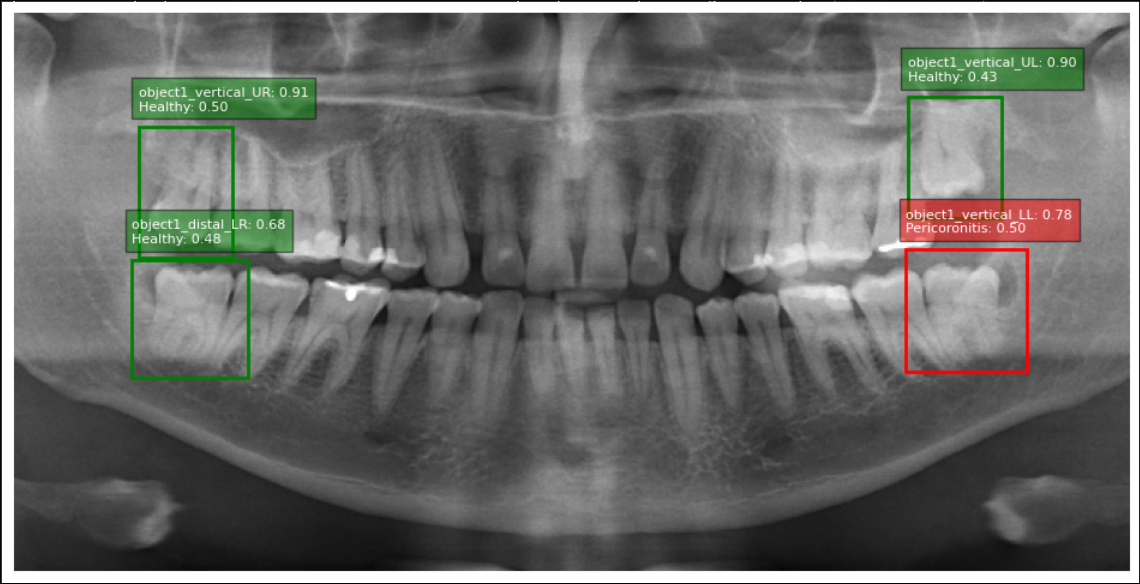

The proposed two-stage deep learning pipeline demonstrates strong potential for automating the detection and localization of pericoronitis in panoramic radiographs by integrating anatomical localization, pathological classification, and explainable AI.(Fig. 2).

Figure 2: Detection, anatomical localization and pathological classification of pericoronitis of third molars

The dual-stage architecture replicates clinical reasoning by first identifying anatomical location of third molars and their Winter’s classification (vertical, mesioangular, horizontal, and distoangular), then analyzing radiological features of pericoronitis. The system efficiently distinguishes between healthy teeth and those affected by pericoronitis, which presents radiographically with distal/mesial bone loss, widened follicular space (>2mm>2\text{mm}), and pericoronal semilunar or circumferential radiolucent lesion. Panoramic radiographs reveal tooth angulation and marginal bone resorption Fig. 2, while advanced cases show abscess formation or osteomyelitis, requiring CT for early inflammation assessment.